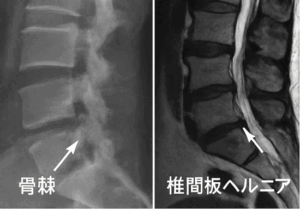

腰にできる骨棘は、加齢や椎間板の変性に伴って生じることが多いと言われています。一方で、変形性腰椎症や椎間板ヘルニア、脊柱管狭窄症といった疾患も似たような症状を示すことがあるため、区別が難しい場合があります。例えば、骨棘が神経を圧迫して痛みやしびれを起こすケースは、椎間板ヘルニアや狭窄症と似た経過をたどることがあるとされています(引用元:International Lumbago Clinic)。

画像検査の役割と限界

レントゲン検査では骨棘の存在や骨の変形を確認しやすいと言われています。しかし、椎間板の状態や神経の圧迫程度までは映し出せないため、必要に応じてMRIが用いられることもあります。MRIでは椎間板の突出や脊柱管の狭さを詳しく把握できるとされていますが、画像所見と実際の症状が一致しないこともあり、検査だけで確定的な判断をするのは難しい場合もあると説明されています(引用元:国立台湾大学)。